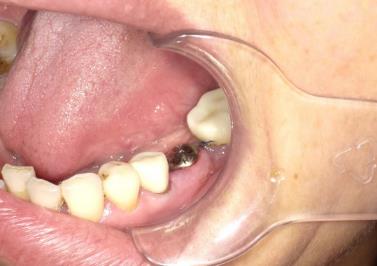

患者,女,45岁,主诉:牙位缺失,要求种植。 现病史:患者左侧下颌36牙缺失多年,因影响咀嚼来我科就诊,要求种植修复。 既往史:患者自述无高血压、糖尿病、心脏病等,否认患有其他全身系统性疾病;否认各类药物、食物过敏史。

检查:36牙缺失。与同名牙对称,邻牙无倾斜或扭转,对合牙无伸长;牙龈无红肿、溃疡;其他牙无龋坏、残根、残冠。 CBCT检查:36牙缺失。

诊断:36牙缺失。 建议:种植修复。 手术记录:常规消毒铺单,局部浸润麻醉,于36牙牙位行横行切口,骨膜剥离器剥开黏骨膜瓣,显露术野。生理盐水冲洗冷却下,球钻定位,植入种植体,旋入愈合帽。 术后拍片,种植体方向好。10天后检查,伤口初步愈合。